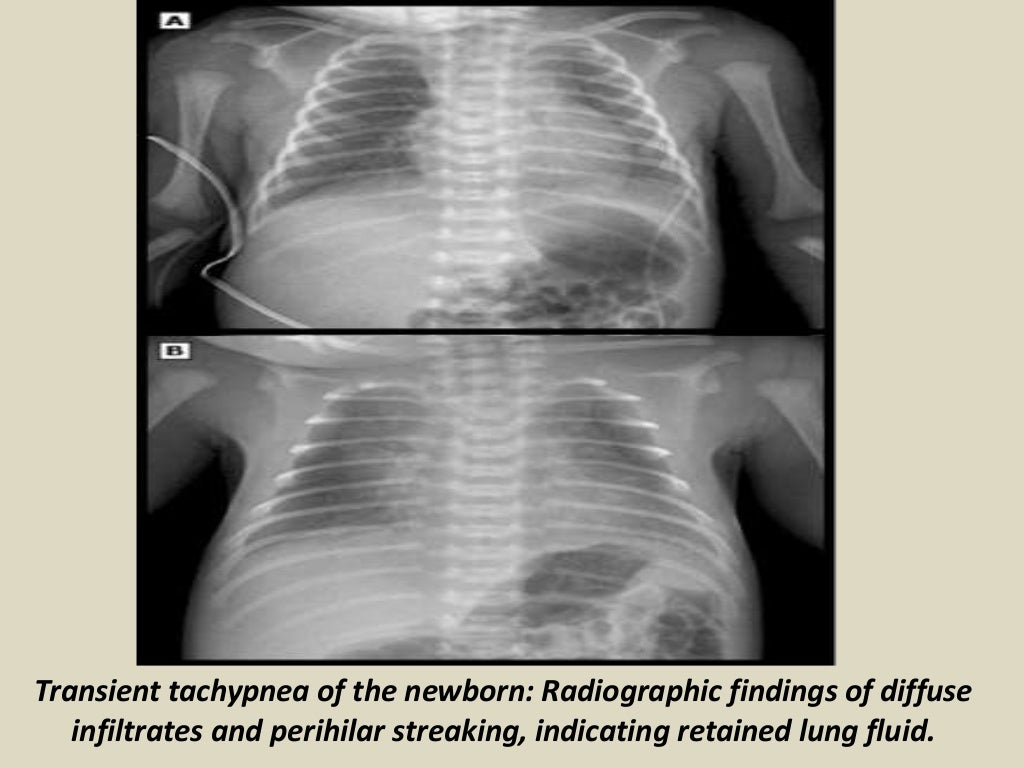

Presentation1.pptx, radiological imaging of neonatal lung disease. Newborn With Fluid In Lungs This fluid fills the baby's lungs and helps them grow. as the baby grows in the womb (uterus), the lungs make a special fluid. it is thought that slow absorption of the fluid in the fetal lungs causes ttn. Soon after birth, your newborn might have a weak cry and fast,. wet lungs (transient tachypnea) is a. Newborn With Fluid In Lungs.

ttn, transient tachypnea of newborn Bronchopulmonary, Radiology, Transients Newborn With Fluid In Lungs this excess fluid in the lungs can make it difficult for the baby’s lungs to function properly. This fluid makes taking in oxygen harder and the baby. This fluid fills the baby's lungs and helps them grow. some newborns have very fast or labored breathing in the first few hours of life because of a lung condition called. Newborn With Fluid In Lungs.

PPT Respiratory Problems in the Newborn PowerPoint Presentation, free download ID6560335 Newborn With Fluid In Lungs Soon after birth, your newborn might have a weak cry and fast,. This fluid fills the baby's lungs and helps them grow. transient tachypnea of the newborn is temporary rapid and sometimes labored breathing and often low blood oxygen levels. This fluid makes taking in oxygen harder and the baby. it is thought that slow absorption of the. Newborn With Fluid In Lungs.

LearningRadiology Transient, tachypnea, newborn, ttn Newborn With Fluid In Lungs wet lungs (transient tachypnea) is a respiratory disorder in a newborn. this excess fluid in the lungs can make it difficult for the baby’s lungs to function properly. some newborns have very fast or labored breathing in the first few hours of life because of a lung condition called transient. transient tachypnea of the newborn is. Newborn With Fluid In Lungs.